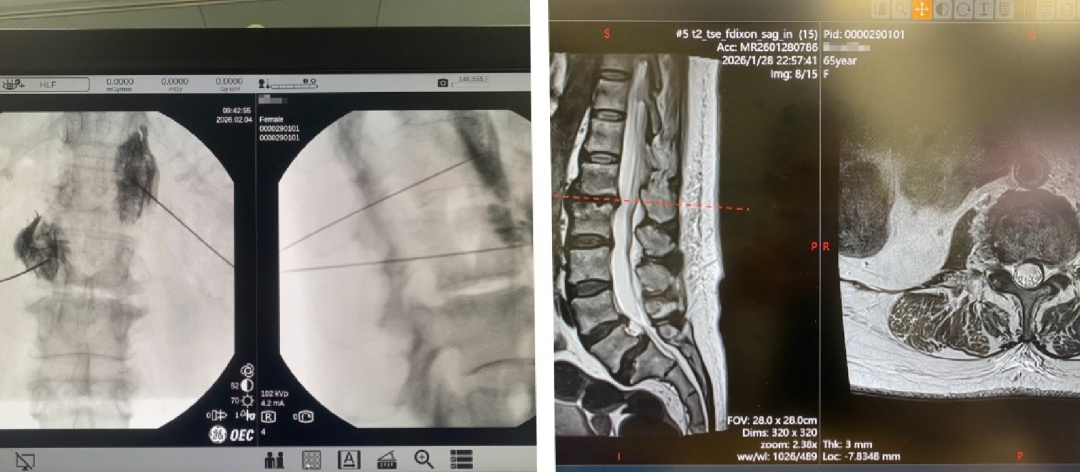

患者既往检查影像

面对患者复杂的基础病及多系统受累情况,传统开放手术风险极高。武百山团队在充分评估患者病情及透析时间后,制定了缜密的手术方案。2026年2月4日,在局部麻醉下,武百山凭借精湛技术和丰富经验,成功为患者实施经皮穿刺腰交感神经节高电压长时程射频微创介入治疗。手术通过两根细针精准作用于病变神经靶点,既解除了神经根刺激症状,又通过调节腰交感神经,显著改善了双下肢血液供应。

疼痛科副主任武百山为患者手术